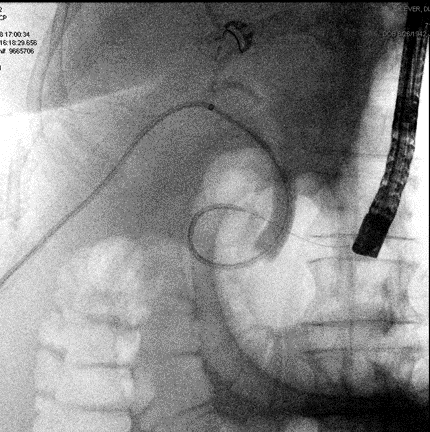

In the IR/GI suite the ERCP scope was advanced to the major papilla under general anesthesia. A glidewire was inserted into the CBD and then passed into the cystic duct. The wire was advanced through the cystic duct through the biloma and into the right posterior ductal system. The IR team had access to the intra-hepatic ducts already through the previously placed PTBD and they percutaneously advanced a snare under fluoroscopic guidance towards the endoscopist's wire to capture the wire and pull it back out the PTBD skin site (see Figure 5 for cholangiogram image). A PTBD was then advanced by IR over the guidewire into the duodenum (Figure 6) and secured into place. Final cholangiogram image showed contrast injected percutaneously traveling through the previous biloma without contrast extravasation and into the cystic duct and duodenum (Figure 7).

Figure 6. A PTBD tube was advanced across the biloma and into the cystic duct down into the duodenum by the IR team.

Figure 7. Final rendezvous cholangiogram showing flow through PTBD through the previous biloma cavity, cystic duct and CBD, finally into the duodenum.